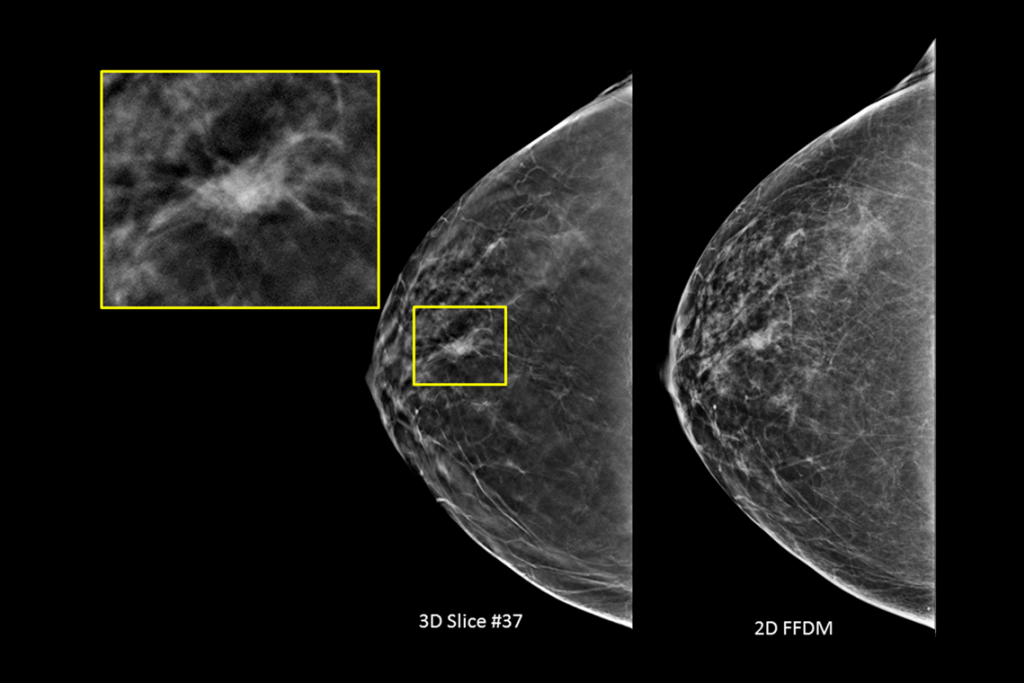

Clinical images of breast scan mammography

Clinical images of breast scan with suspicious Lesion